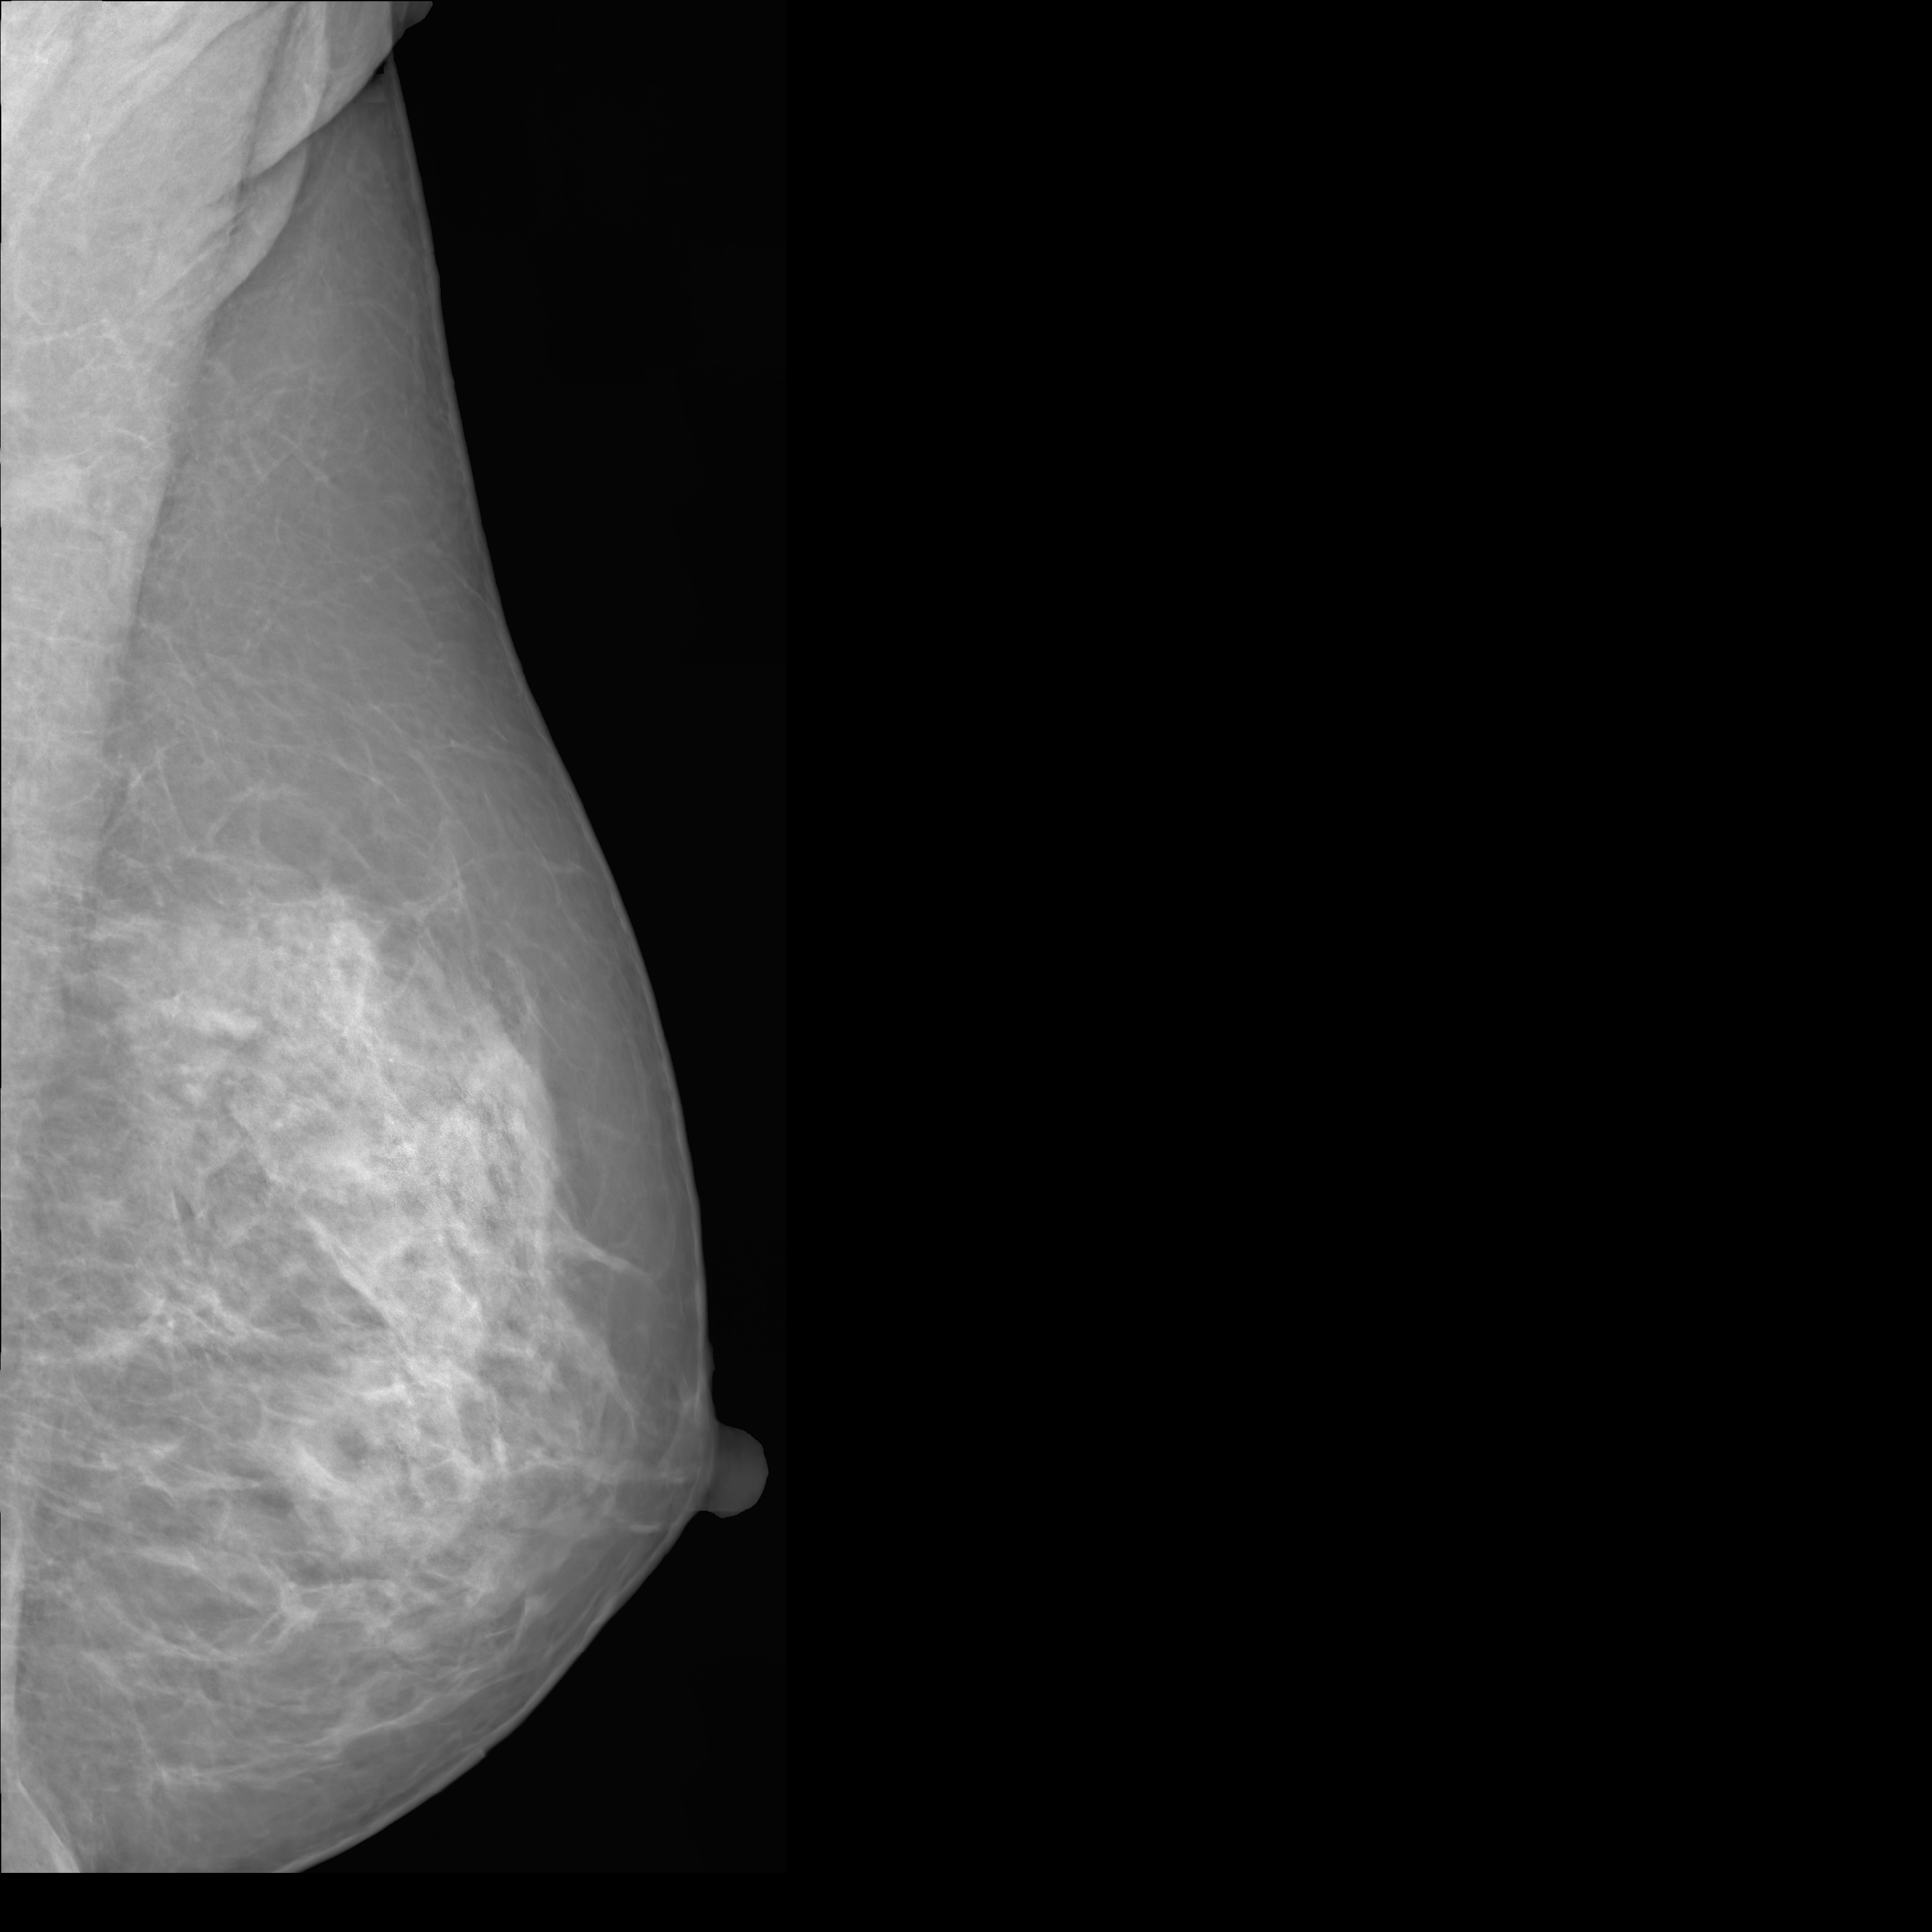

To overcome these challenges, this paper introduces MAMmography ensemBle mOdel (MAMBO), a novel approach that leverages an ensemble of diffusion models to generate mammography images at their native resolution. MAMBO uses a patch-based approach for generation which is conditioned both on local and global (full-image) context. In a nutshell, MAMBO involves the development of three distinct models: the first generates “standard”-resolution ( pixels) images to provide global context; the second increases the resolution to create local context for the target patch; and the third combines the outputs of both models to guide the generation of high-resolution patches, which are then reconstructed into a full-resolution synthetic mammogram. An example of a synthetic image generated by MAMBO is shown in Fig. 1. The image presents details at multiple resolutions, corresponding to the global and local contexts, and individual patch at full resolution. To the best of our knowledge, this is the first work to propose a diffusion model approach for generating very high-resolution synthetic mammograms.

What MAMBO can achieve in terms of qualitative results is presented in Fig. 1 and Fig. 3(d). MAMBO is able to generate high-quality images that are visually indistinguishable from the originals, representing plausible mammogram data to layman eyes. Results are also validated with expert radiologists, with quantitative results shown in Sec. 4.2.

Fig. 3(d) illustrates what MAMBO can achieve in terms of whole mammogram generation. When using global and local context data extracted from an original image, the denoised image (Fig. 3(b)) is difficult to distinguish from the original (shown in Fig. 3(a)). When providing only the original global context and generating local context and target patches from noise, we still observe good results, as we show in Fig. 3(d).